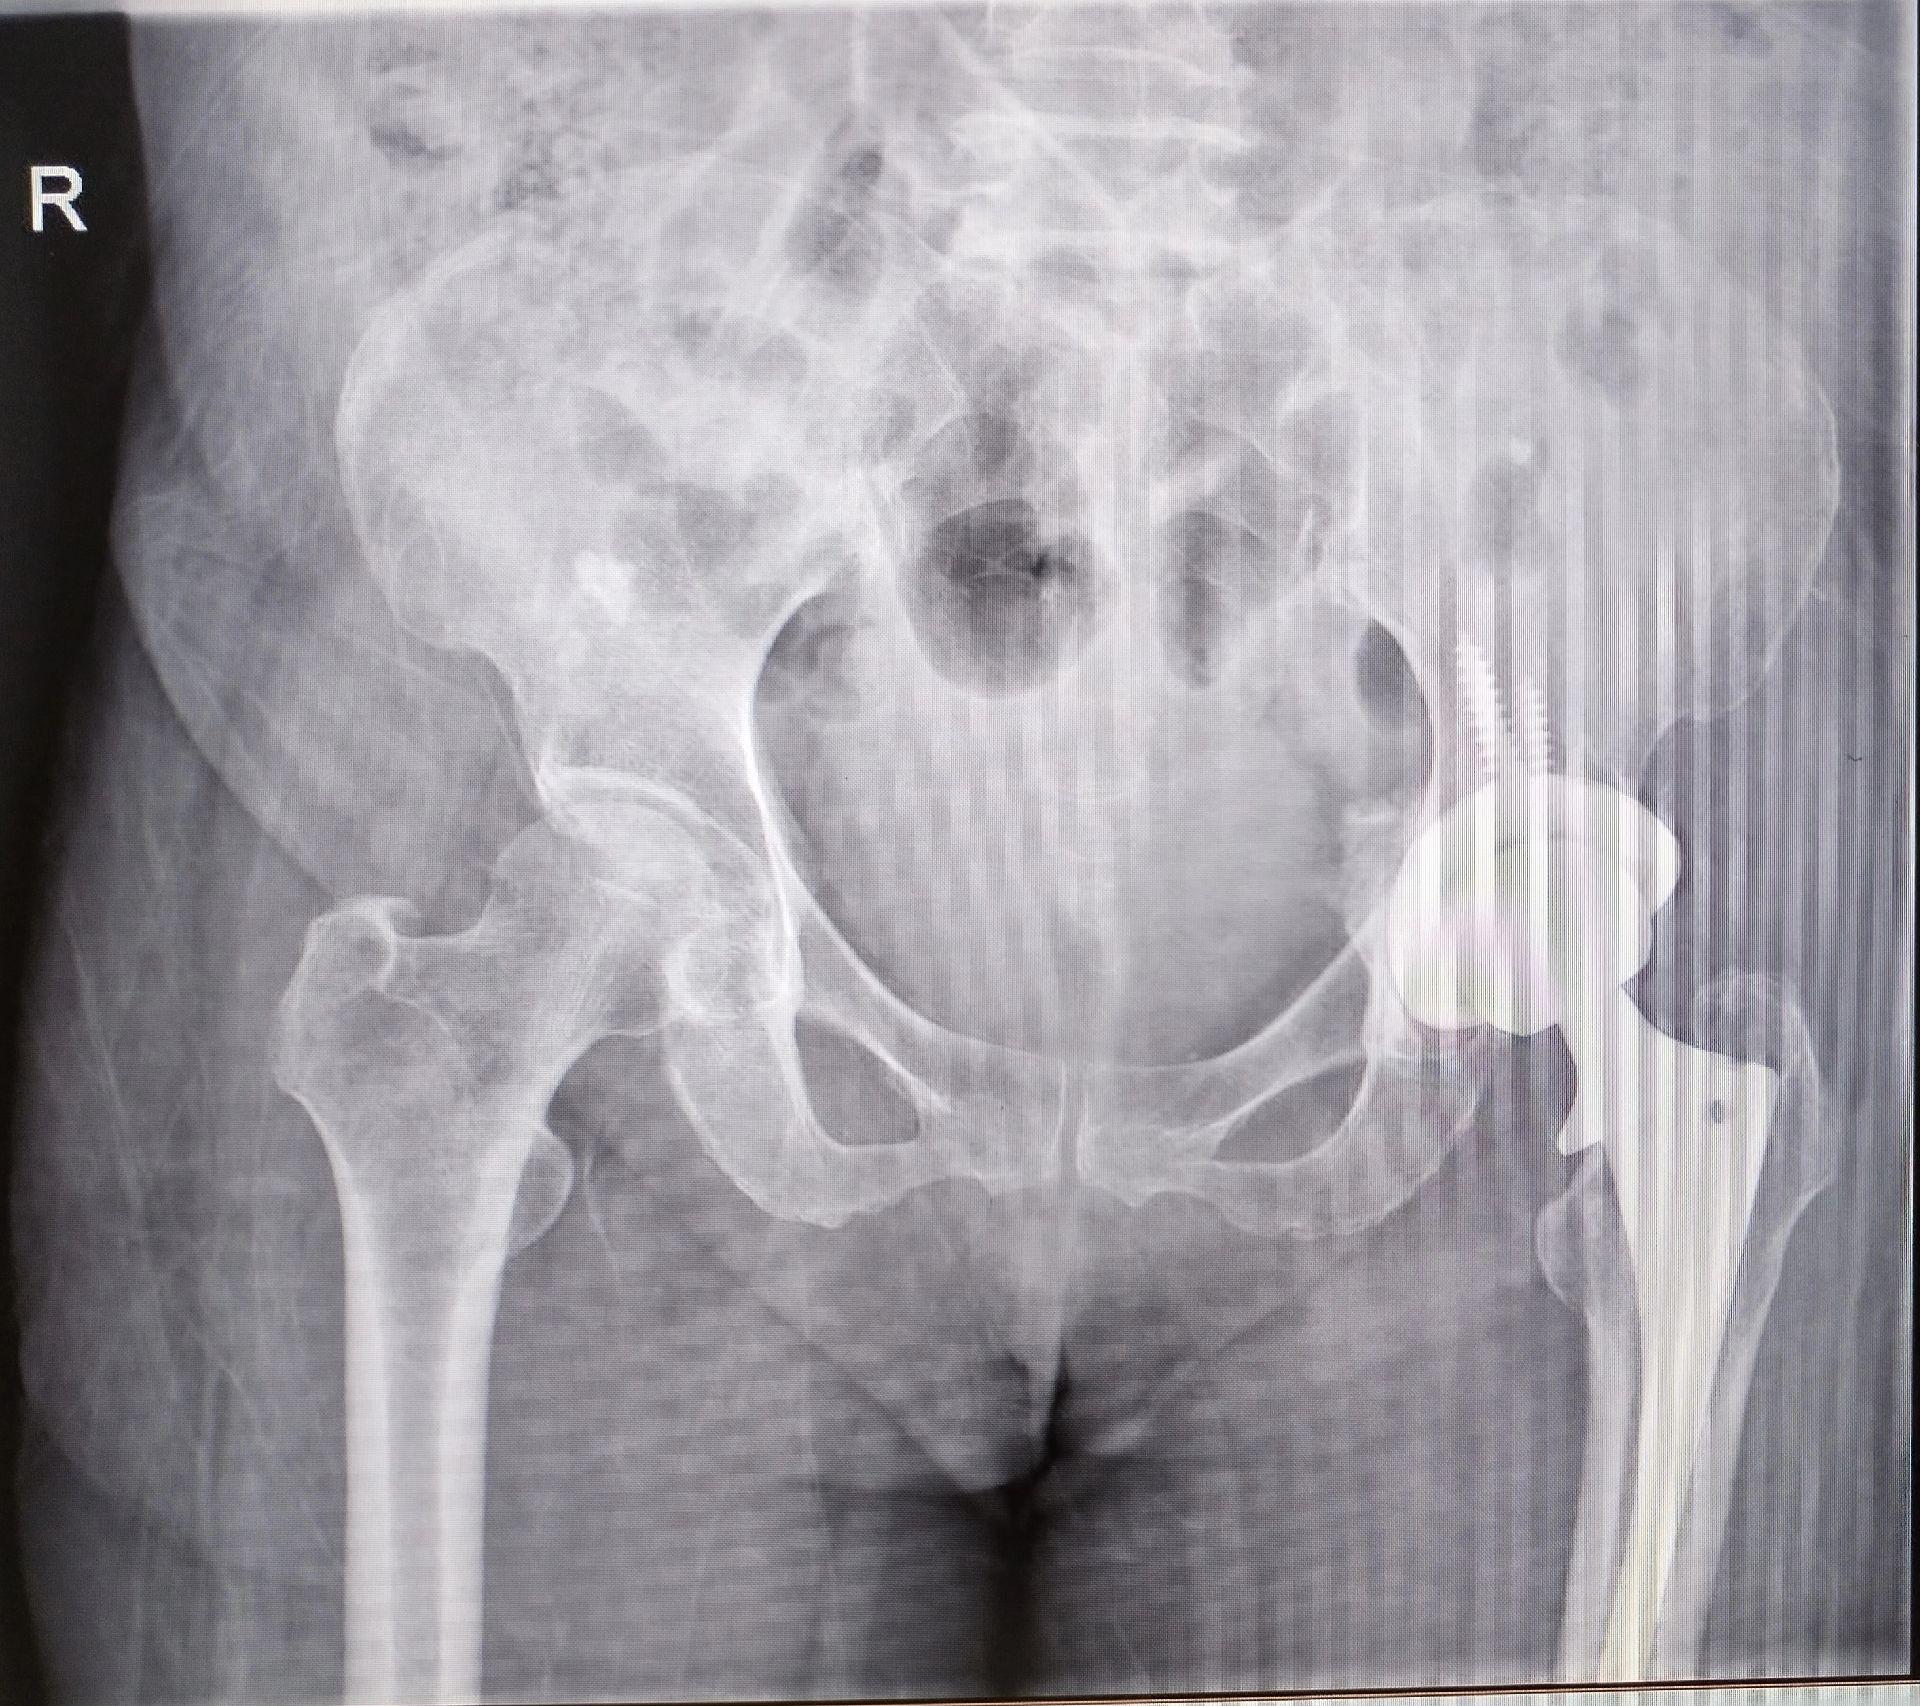

髋关节翻修。髋关节置换术后(外院)4年,磨损颗粒导致的无菌性松动,一期翻修,2天下床活动。磨损有好多因素,材质、体重、活动量等等。